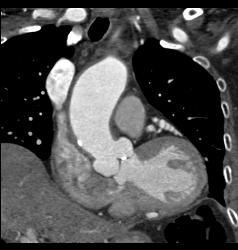

Prior Myocardial Infarction and Dilated Root